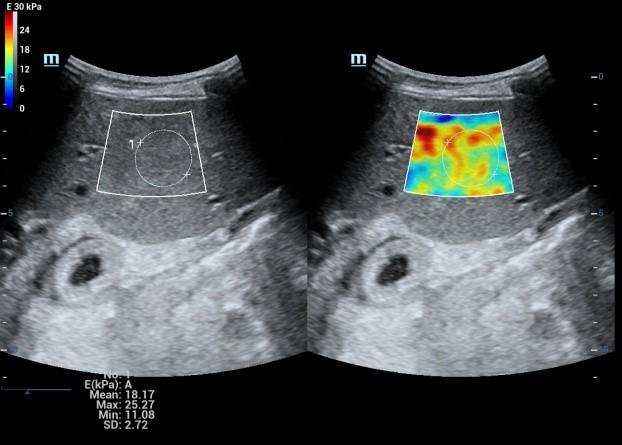

• High End SHEAR WAVE ELASTOGRAPHY For LIVER FIBROSIS/THYROID MALIGNANCY/BREAST CANCER

Liver Elastography